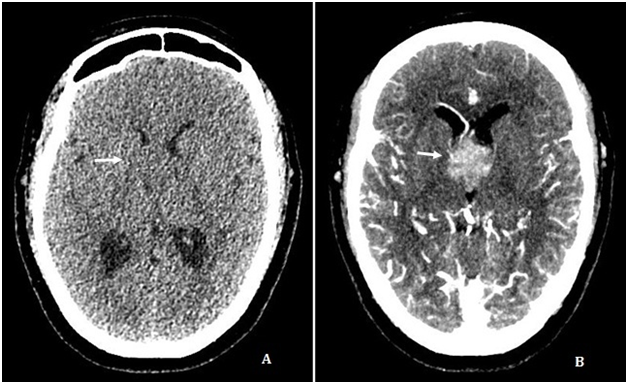

A cerebral angiotomography showed a round not calcified enhancing mass inside the third ventricle (Figure 1A) (Figure 1B). The Magnetic Resonance Imaging (MRI) revealed mild hydrocephalus and a heterogeneous, lobulated, expansive enhancing lesion inside the third ventricle, with intermediate T2 signal intensity, small cystic areas and microbleeding (Figure 2‒4). The patient underwent External Ventricular Derivation (EVD) with improvement of the initial symptoms.

Figure 1 Axial CT scan without intravenous contrast (A) and Maximum Intensity Projection (MIP) reconstruction with intravenous contrast (B) showing a enhancing round mass inside the third ventricle lumen (arrow).